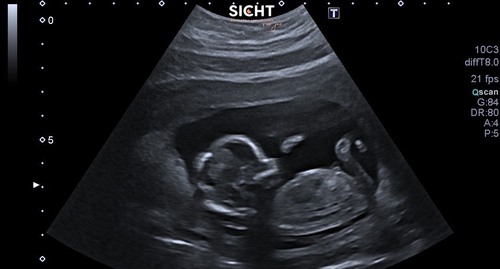

Iemand hier een idee ( vorige topic werd helaas gesloten. Mijn vrouw is 12+4 weken hieronder)